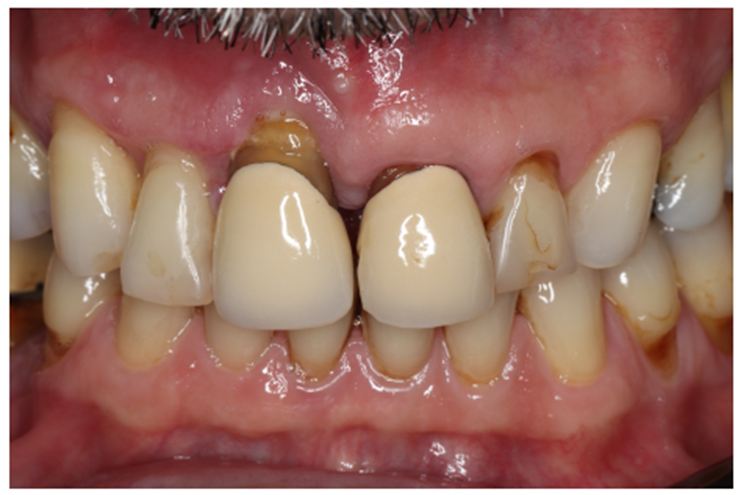

Paciente RV, do sexo masculino de 52 anos, compareceu a nossa clínica com queixa estética e funcional dos dentes incisivos centrais superiores. No exame clínico observou-se doença periodontal severa com presença de bolsa periodontal e perda óssea marginal maior do que 7 mm (Figura 1). Foi realizado em nossa escola (Beo – Ensino Odontológico Avançado) uma tomografia computadorizada para melhor planejamento cirúrgico do caso, onde confirmamos a necessidade de regeneração óssea guiada com membrana Cytoplast com reforço de titânio, devido à perda óssea vertical maior do que 7 mm (Figura 2). Após definição do planejamento cirúrgico, foi realizado a exodontia dos incisivos centrais superiores, limpeza cirúrgica da região e osteotomia periférica para melhor preparo do leito receptor do material de enxertia de lenta reabsorção Bio-Oss (Geistlich) e da membrana Cytoplast com reforço de titânio 30 mm X 40 mm (Figuras 3,4 e 5). Após estabilização da membrana, foi realizado a sutura com fio do tipo Cytoplast 3.0 mm devido a sua alta plasticidade, diminuindo o risco de deiscência de sutura (Figura 6).